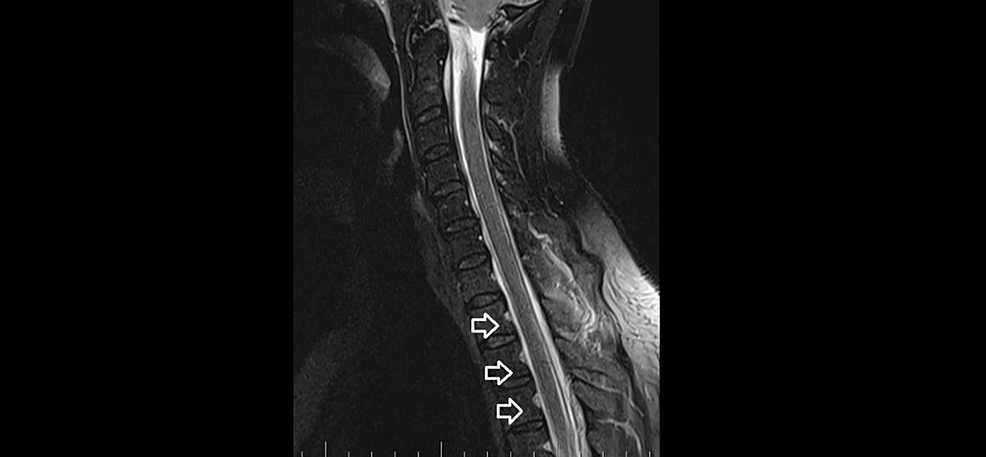

Brain and C spine MRI (Figures 5, 6) on September 4, 2023, showed a total regression of SIH signs. MRI myelography showed complete resorption of the SLEC, with no CSF leak. The patient was without any clinical symptoms or headache. She continues to work as a nurse. Her quality of life has improved significantly.